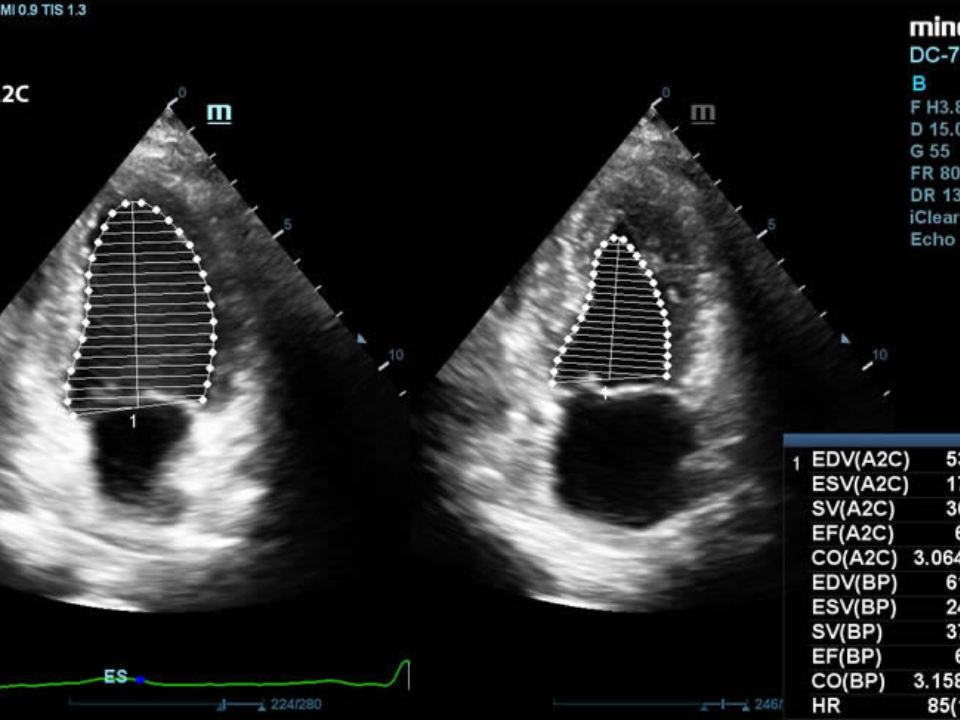

Echo Boost

MindrayŌĆÖs unique adaptive signal processing technology with intelligent echo detection, designed to utilize the native signal-to-noise information to enhance the weak echo signals while suppressing the surrounding clutter noise, providing more balanced image brightness and improved visualization of myocardium tissue layers.